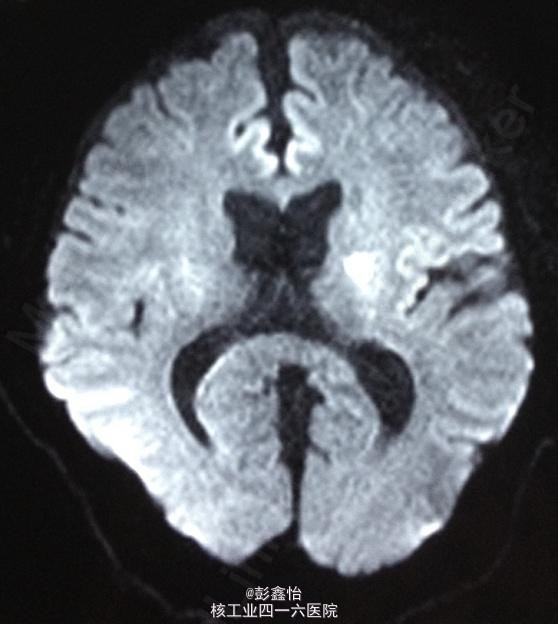

因患者无明显肢体抽搐及局部泛化过程,脑电监测正常,基本可除外癫痫发作。诊断TIA,予以阿司匹林、他汀降脂等治疗,但TIA继续发作。 追加血管评估,但TCD、DSA、颈部血管超声均未发现异常,在原有治疗基础上,予以双抗、改善循环、营养神经加强治疗 但患者仍频繁发作TIA,3天内共发作20余次。判断为治疗抵抗,继续加用抗凝、脑保护,最后加用羟乙基淀粉扩容治疗后发作终止,但患者出现右侧肢体轻偏瘫。 复查DWI:左侧基底节区出现急性梗死灶; 复查MRA、DSA均未见异常。